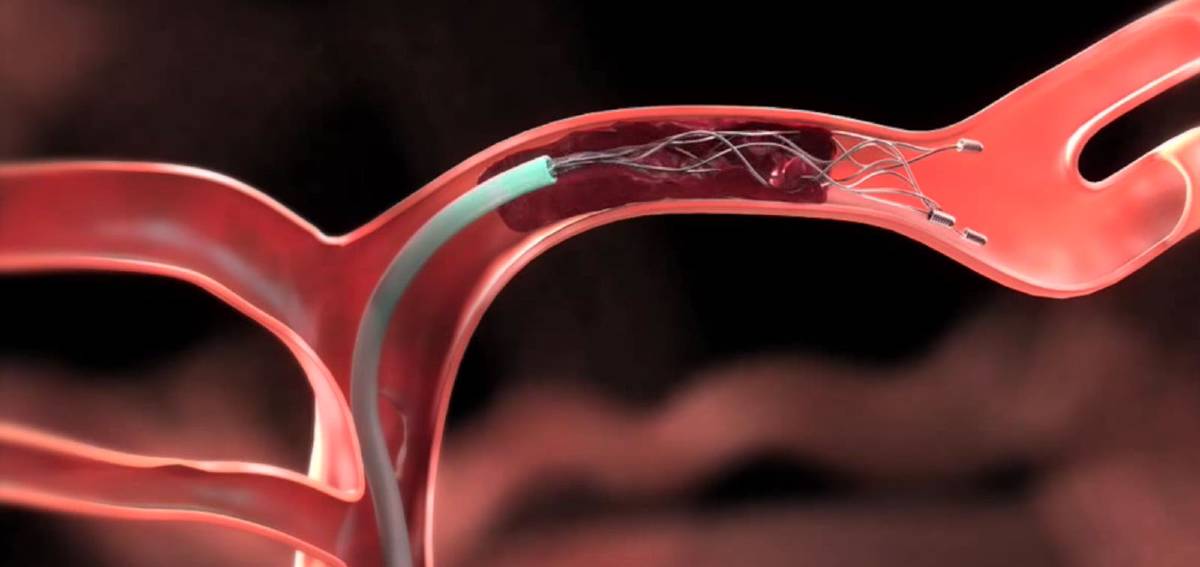

Mechanical thrombectomy is an emergency minimally invasive procedure used to treat acute ischemic stroke caused by a large artery blockage in the brain. It is performed when blood flow is suddenly interrupted, leading to brain tissue damage and neurological deficits.

Using catheter-based devices, the clot is physically removed, restoring circulation, limiting brain injury, and significantly improving recovery when performed within the critical treatment window.